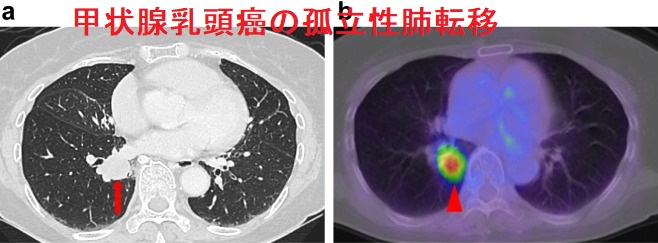

甲状腺乳頭癌 肺転移 CT画像。中-下肺野に、小粒状陰影が多数あります。

甲状腺癌の肺転移様式として、両側肺に、びまん性多発小結節を形成するのが普通です(上記肺X-p、CT画像)。孤立結節型は11.4%とされます。

1cm程度の甲状腺乳頭癌・1cm 以下の甲状腺微小乳頭癌の肺転移は、片肺の孤立性結節のみです。しかもTBLB 組織診でサイログロブリン免疫染色も陰性のため、原発性肺癌との鑑別不可能です。当然、原発性肺癌として肺切除され、術中迅速病理診断で甲状腺乳頭癌肺転移が確定した時点で手術終了。

甲状腺乳頭癌自体も

- 10.5mm大の大きさで、明らかなリンパ節転移も認めなかった(第57回 日本甲状腺学会 P1-068 肺病変のサイログロブリン免疫染色が陰性であったため原発性肺癌との鑑別に苦慮した甲状腺乳頭癌孤立性肺転移の一例)

- 潜伏性(occult papillary thyroid carcinoma)だった[Thorac Cancer. 2016 Mar;7(2):261-3.][Nihon Naibunpi Gakkai Zasshi. 1991 Jun 20;67(6):655-65.]

甲状腺乳頭癌の孤立性肺転移CT・PET-CT画像[Thorac Cancer. 2016 Mar;7(2):261-3.]